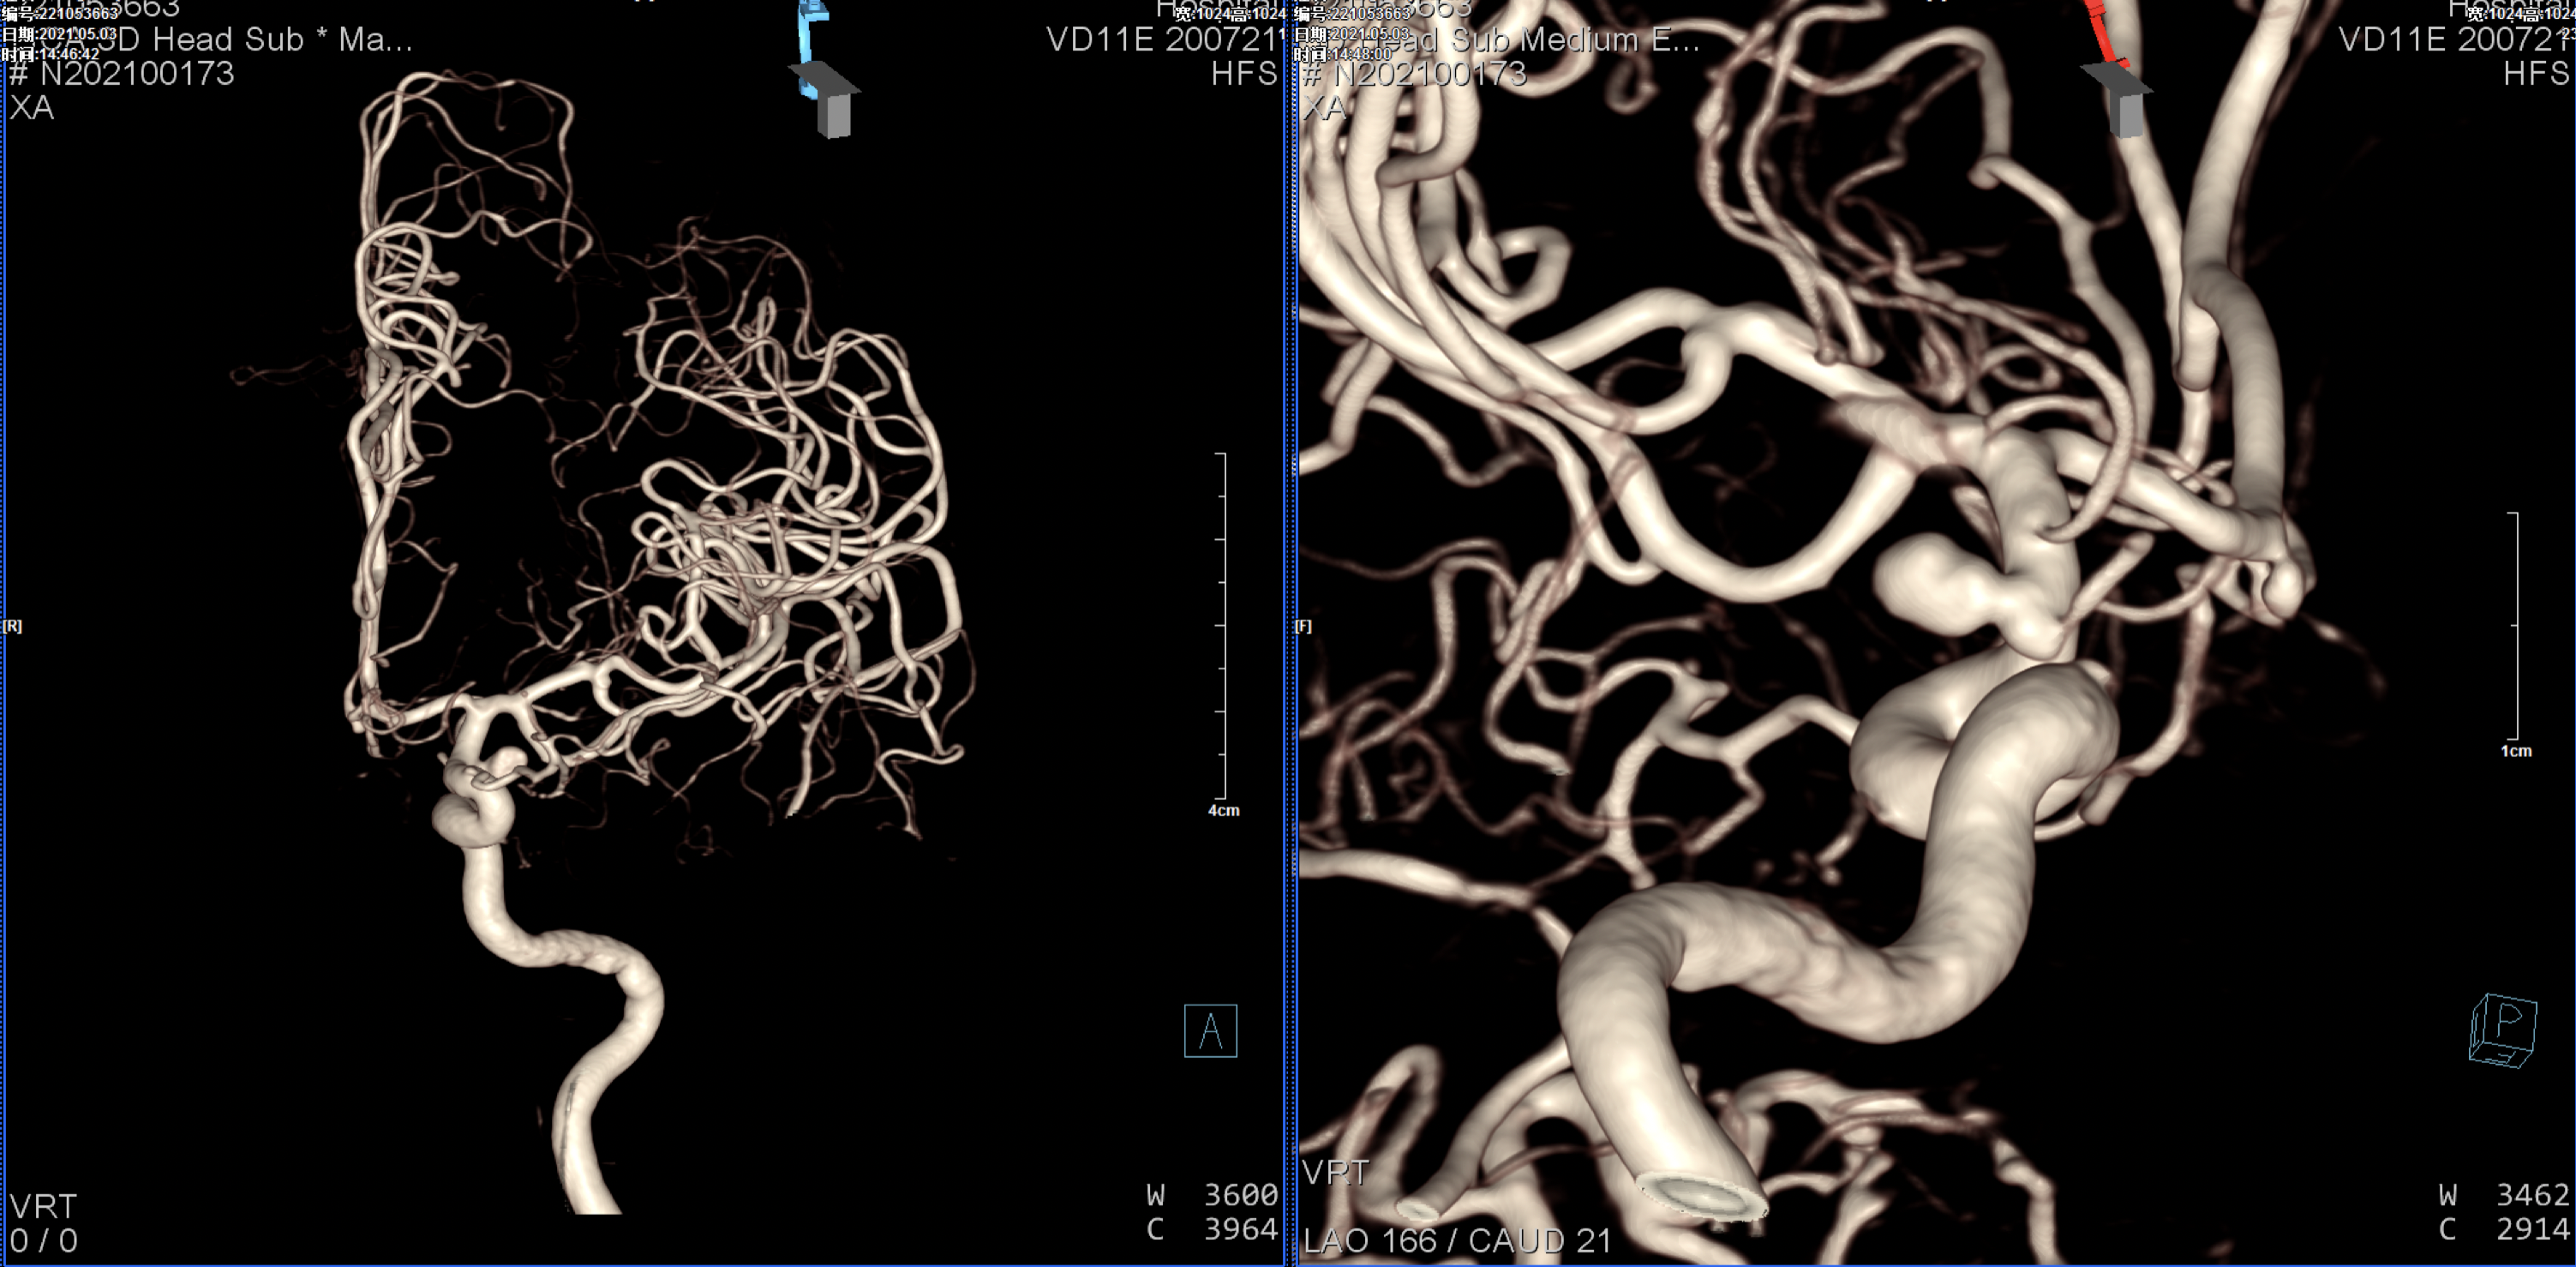

右侧颈内动脉三维重建:颈内动脉多发动脉瘤(眼动脉段及后交通段)